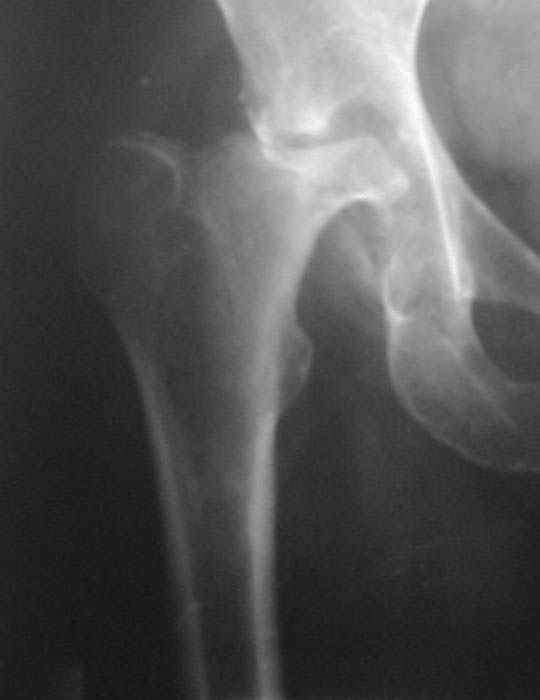

Уважаемые коллеги! Прошу Вас оказать консультативную помощь. Женщина, 44 года, инвалид 3 группыДиагноз: СКВ, асептический некроз головок обеих бедернных костей, двусторонний артроз 3-4 ст., болевой синдром, приводящая контрактураправого тазобедренного сустава, хронический волчаночный гепатит, спленомегалия, анемия, СКВ с 2002 года (подтверждена наличием lupus-клеток), получала специфическую терапию, медрол 16 мг/сут. Боли в левом тазобедренном суставе появились в сентябре 2003 года. Динамика отражена на рентгенограммах. В марте 2004 года - синдром Мэллори-Вейса, кровотечение остановлено эндоскопически. Объективно: кожа бледная, пастозность, отечность лица, высыпания на лице практически отсутствуют. Печень +6 см, селезенка не пальпируется. АД140/80, пульс 100, дыхание 15.

Ходит с тростью, хромота. Объем движений в суставах: справа - сгибание 90, разгибание 170, отведение 0, приведение 20, внутренняя ротация 15;слева - сгибание 90, разгибание 180, отведение 0, приведение 20, внутренняя ротация 0, наружная ротация 20. ЭКГ - отклонение ЭОС влево, гипертрофия левого желудочка, дистрофические изменения миокардаОбщий анализ крови: Э. 3,6, Hg 100, цп. 0,83, л.7,3, э.1, п.3, с.72, л.19, м.5, СОЭ 5 Общий анализ мочи: объем 120,0, уд.вес 1008, желтый, р-ция кислая, сахар/белок/цилиндры нет, эпителий и эритроциты единичные, Л.1-2, солиоксалатовые в небольшом к-ве. Биохимический анализ крови Билирубин 11,5 ммоль/л (прямой 0, непрямой 11,5), АСТ 0,24, АЛТ 0,61, протромбиновый индекс 100, рекальцификация 150, фибриноген 1,99,толерантность 8, фибринолитическая активность 240, общий белок 74,3, сиаловые кислоты 250 ед., С-реактивный белок 0. Пациентка желает выполнить тотальное эндопротезирование. Допустимо ли выполнение подобной операции? При каких условиях, дополнительной терапии? Особые предоперационные мероприятия? Личный опыт? Комментарии?Мнения? Заранее благодарю!!! С уважением, А.В.Владзимирский Донецкий НИИ травматологии и ортопедии